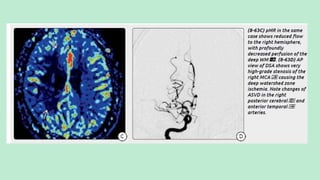

 CT perfusion maps

of cerebral blood volume

(a) and cerebral blood flow (b)

show, in the left hemisphere,

a region of decreased blood

volume (white oval) that corresponds

to the ischemic core

and a larger region of decreased

blood flow (black oval

in b) that includes the ischemic

core and a peripheral

region of salvageable tissue.

The difference between the

two maps (black oval white

oval) is the penumbra.

Ischemic core Region of dec. blood

Penumbra

Well perfused area